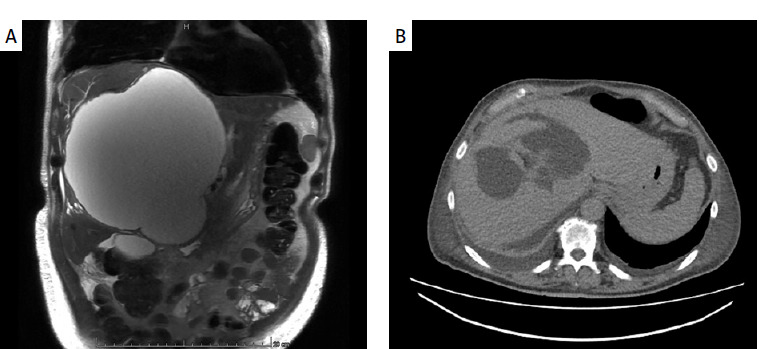

Raoultella planticola as a rare cause of liver abscess.

Abstract Image